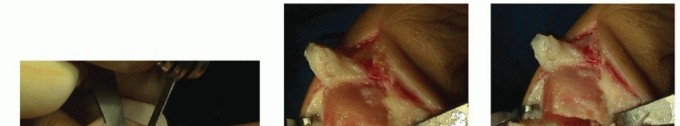

I use a Y-shaped incision over the medial face of the MTP joint capsule, creating three distinct flaps that I reapproximate at the completion of the procedure to achieve optimal tensioning (TECH FIG 1A,B).

A short V capsular flap attached to the base of the hallux proximal phalanx may be used as an anchor to correct the deformity. I always preserve the relatively thin dorsal capsular flap continuous with the lateral capsule to maintain the blood supply to the first metatarsal head. The stout plantar capsular flap attached to the sesamoids serves to reestablish the optimal first metatarsal head-sesamoid position when tensioned after completion of the osteotomy.

TECH FIG 1 • A. The Y figure over the medial face of the MTP joint demarcating the capsular flaps. B. Following the Y figure, the articular capsule is divided to create the three flaps: a V flap attached to the base of the proximal phalanx, a thin dorsal flap, and a strong plantar flap. -